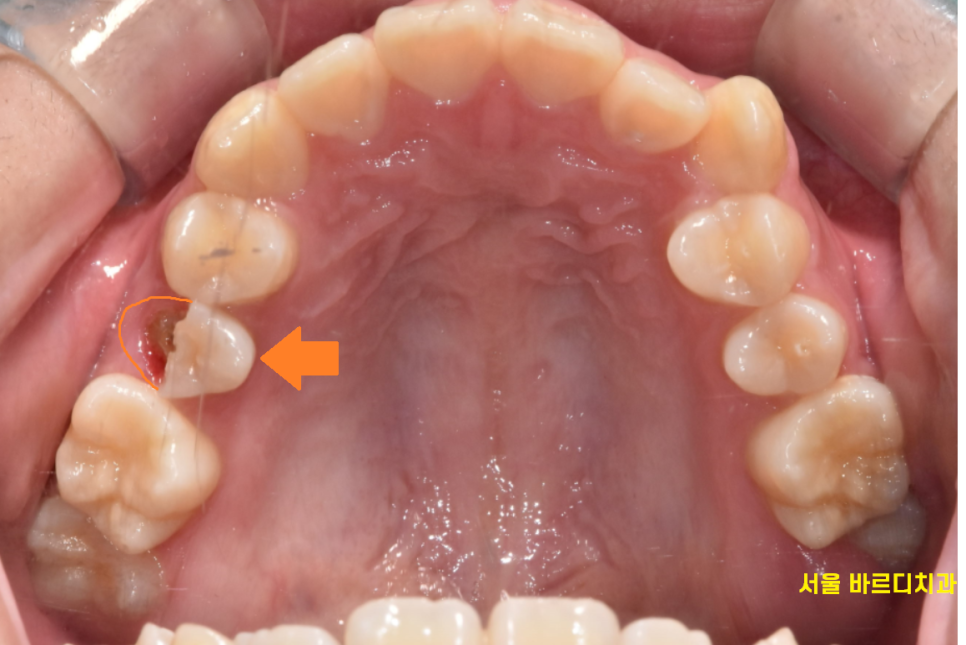

치아가 골절됐어요

급하게 치아가 세로로 골절 되었다고

강일동 치과에 연락을 주신 환자분입니다.

정확히 치아가 절반으로 나누어졌습니다.

치아가 쪼개지기도 하고

치아 골절 발생